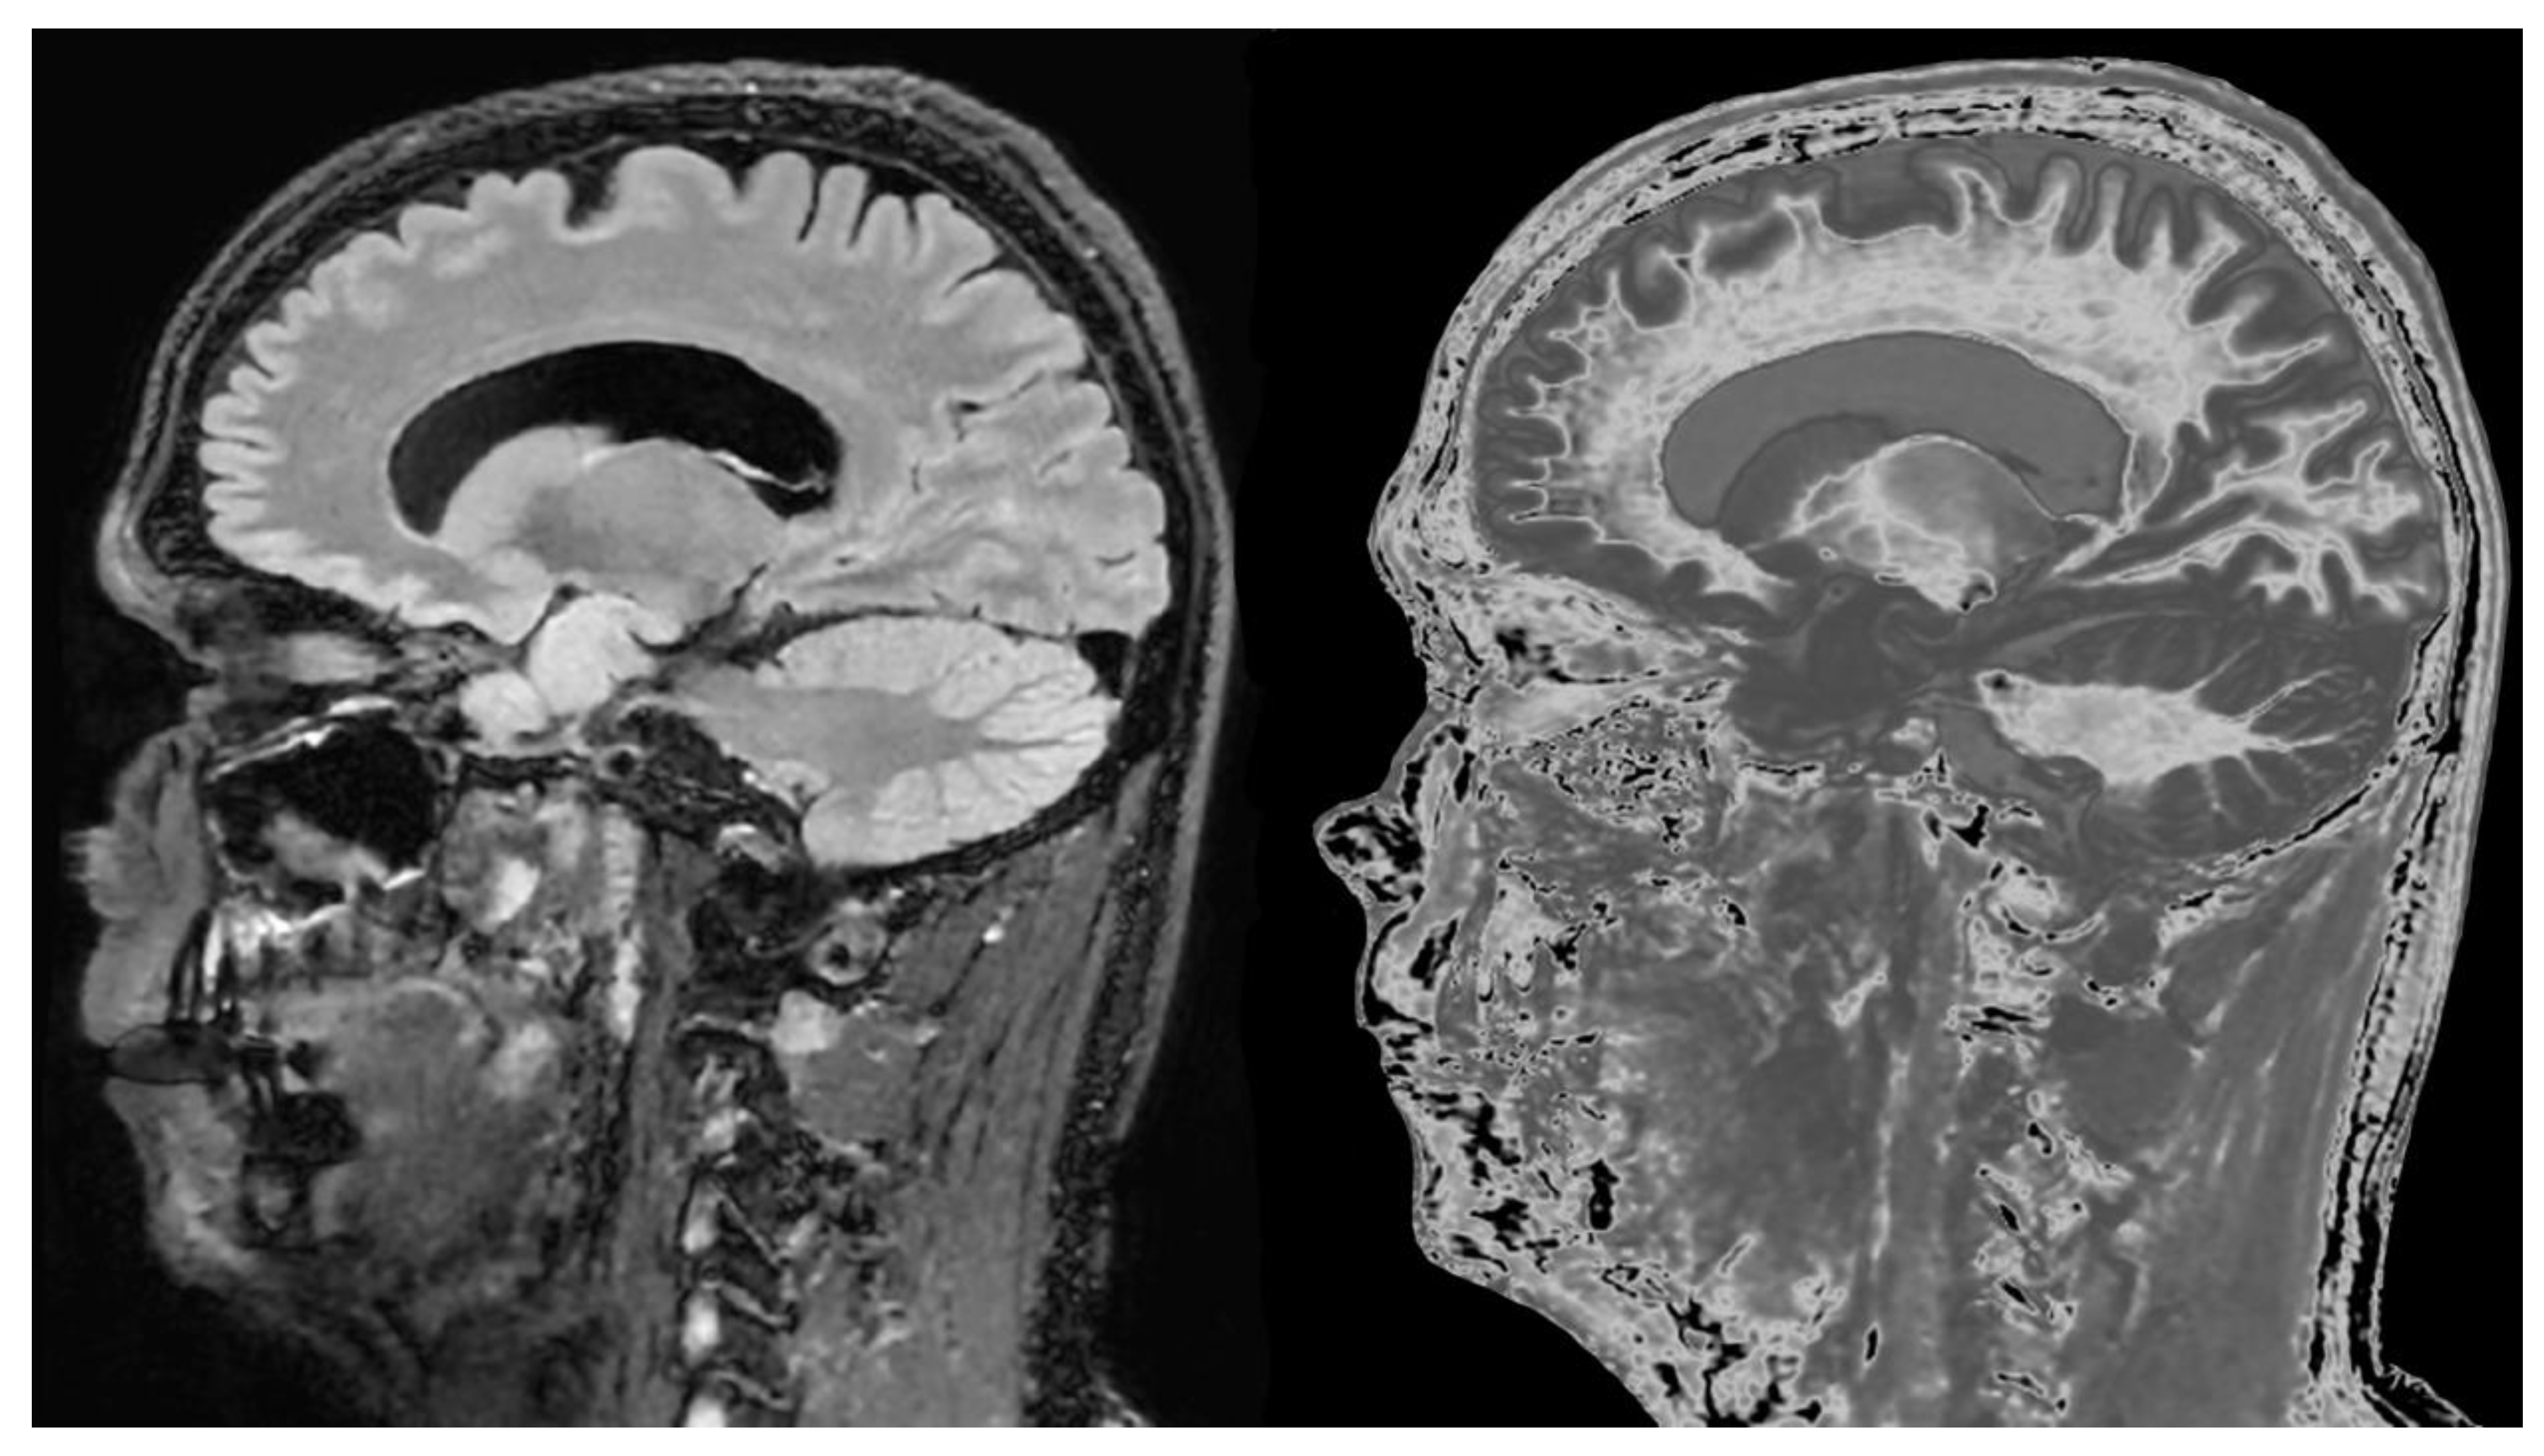

Figure 18.

76-year-old female patient in remission with a diagnosis of MS. Sagittal 3D T2-FLAIR (A) and 3D wide mD dSIR (T1-BLAIR) (B) images. The T2-FLAIR image shows a poorly defined area of increased signal in the cervical cord (arrow). The T1-BLAIR image shows a high contrast lesion with sharply defined („punched out”) boundaries in the cervical cord (lower three arrows). This is much more extensive than in (A). An additional lesion is seen in the medulla on the T1-BLAIR image in the region of the area postrema (highest arrow) (B) but not on the T2-FLAIR image (A). The extended lesion in the cervical cord and the lesion in the area postrema raise the possibility of neuromyelitis optica spectrum disorder. Other conventional sequences such as T2-wSE or STIR may perform better than T2-FLAIR in the cervical cord.